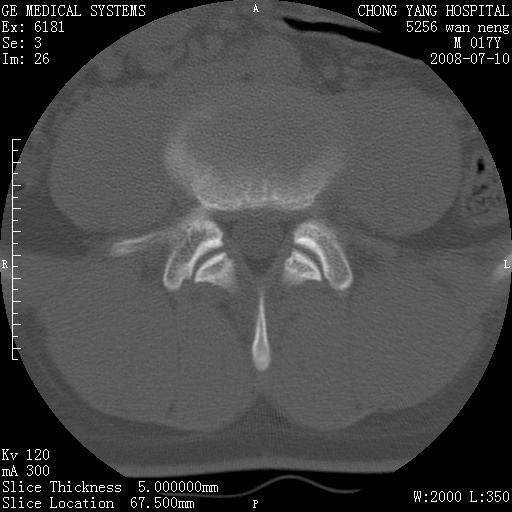

腰3、4椎弓崩裂

腰3、4椎弓不连

支持:腰3、4椎弓峡部崩裂。

腰3、4椎弓峡部不连

支持:腰3、4椎弓峡部崩解。

腰3、4,如受过外伤则为陈旧骨折,否则为骨质不连

图片漂亮,目前也只能看到腰3、4骨质不连

腰3、4椎弓峡部裂。

腰3、4椎弓峡部裂。支持

重建图像见多个椎弓峡部不连(不足为据),平扫未见异常。

支持腰3、4椎弓峡部崩裂。